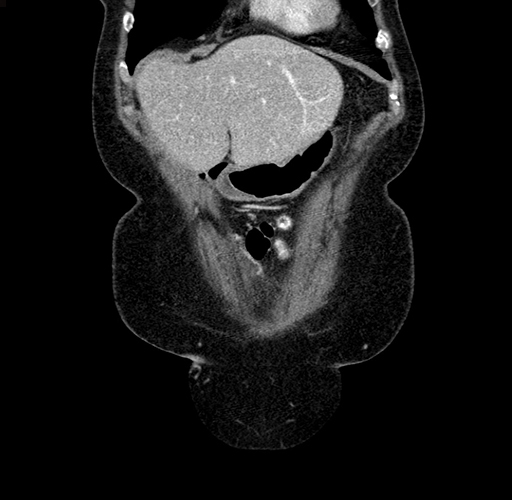

Coronal Venous